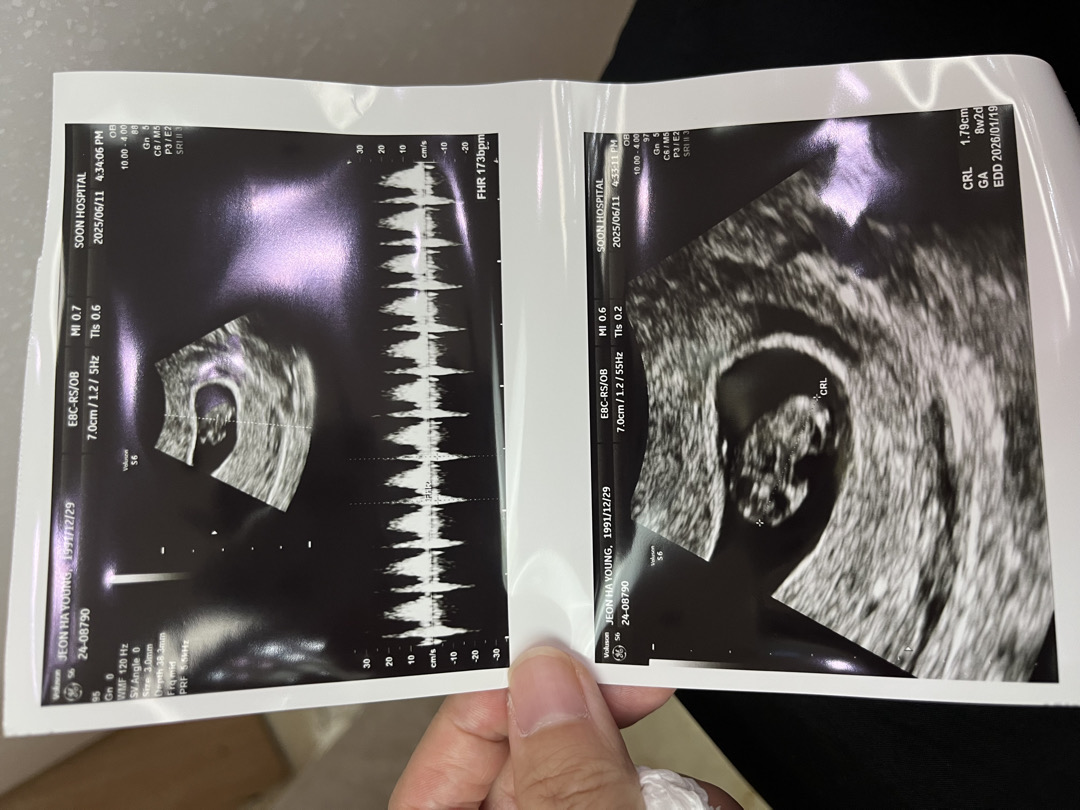

8주2일 심장소리 듣고 왔어요:) + 걱정

눈물이 핑 ㅜ 대견하더라고요 1.79cm , 심박173bpm 잘크고 있다고 하셨어요 자궁선근증이 원래도 있었는데 내막증도 살짝 보인다고 하시네요 ㅠ 아기가 크는데는 이상 없겠죠? 걱정되네요